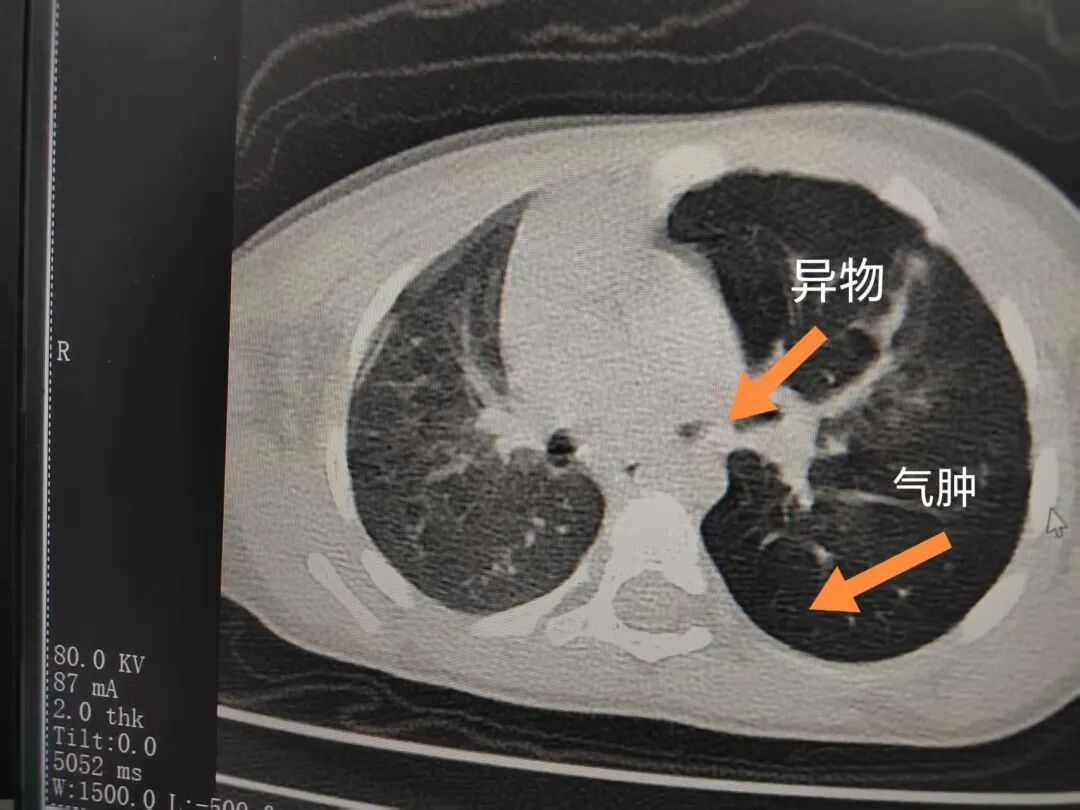

三天后(11月13日),趙寶出現(xiàn)高熱、咳喘加重,家長著急了,再次帶他來到醫(yī)院。CT檢查顯示左肺過度充氣,左肺上下葉支氣管主干見不規(guī)則高密度影,左肺上葉可見大片狀密度增高影,縱隔窗實(shí)變,提示為“左側(cè)支氣管內(nèi)異物并繼發(fā)性改變,左肺上葉舌段肺膨脹不全”。

市二院小兒呼吸內(nèi)科副主任楊亞娟介紹,異物誤入氣道可能導(dǎo)致氣道阻塞,嚴(yán)重時可引發(fā)窒息,甚至危及生命。若異物進(jìn)入支氣管,造成不完全堵塞,可引起阻塞性肺氣腫;如完全堵塞支氣管,則可能導(dǎo)致肺組織萎縮,形成肺不張。此外,若異物存留時間較長,或?yàn)橹参镄援愇?,容易合并?xì)菌感染,產(chǎn)生膿性分泌物,進(jìn)而發(fā)展為肺炎。她強(qiáng)調(diào),盡早診斷并取出異物,是減少并發(fā)癥、降低病死率的關(guān)鍵。